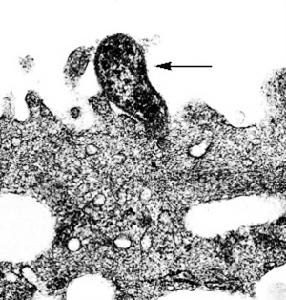

形態結構支原質體的大小為0.2~0.3um,可通過濾菌器,常給細胞培養工作帶來污染的麻煩。無細胞壁,不能維持固定的形態而呈現多形性。革蘭氏染色不易著色,故常用Giemsa染色法將其染成淡紫色。細胞膜中膽固醇含量較多,約占36%,對保持細胞膜的完整性具有一定作用。凡能作用於膽固醇的物質(如二性黴素B、皂素等)均可引起支原質體膜的破壞而使支原質體死亡。

支原質體(Mycoplasmal)是目前所能發現的能在無生命培基中生長繁殖的最小的微生物。 支原質體體形多樣,基本為球形,亦可呈球桿狀或絲狀,其菌落呈針尖大小,故又稱之為微小支原質體。支原質體特點是無細胞壁及前體,細胞器極少。DNA的G C含量低,菌體內具有非常小的染色體組,其分子量約為45×108,菌體細胞大小約為0.2-0.3μm,很少超過1.0μm。由三層蛋白質和脂質組成的膜樣結構以及一層類似毛髮結構組成。支原質體由二分裂繁殖,形態多樣。支原質體用普通染色法不易著色,用姬姆薩染色很淺,革蘭氏染色為陰性。支原質體可在雞胚絨毛尿囊膜上或細胞培養中生長。用培養基培養。營養要求比細菌高。由於它沒有細胞壁,因此對影響細胞壁合成的抗生素,如青黴素等不敏感,但紅黴素、四環素、卡那黴素、鏈黴素、氯黴素等作用於核蛋白體的抗生素,可抑制或影響支原質體的蛋白質合成,有殺傷支原質體作用,支原質體對熱抵抗力差,通常55℃經15分鐘處理可使之滅活。石碳酸,來蘇兒易將其殺死。在培養基中置入脲素並以硫酸錳作指示劑極易與其他支原質體作出鑑別。